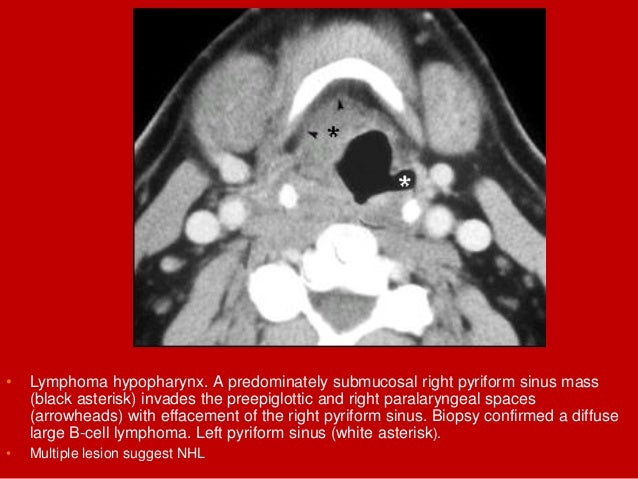

73. 73. • Lymphoma hypopharynx. A predominately submucosal right pyriform sinus mass (black asterisk) invades the preepiglottic and right paralaryngeal spaces (arrowheads) with effacement of the right pyriform sinus. Biopsy confirmed a diffuse large B-cell lymphoma. Left pyriform sinus (white asterisk). • Multiple lesion suggest NHL